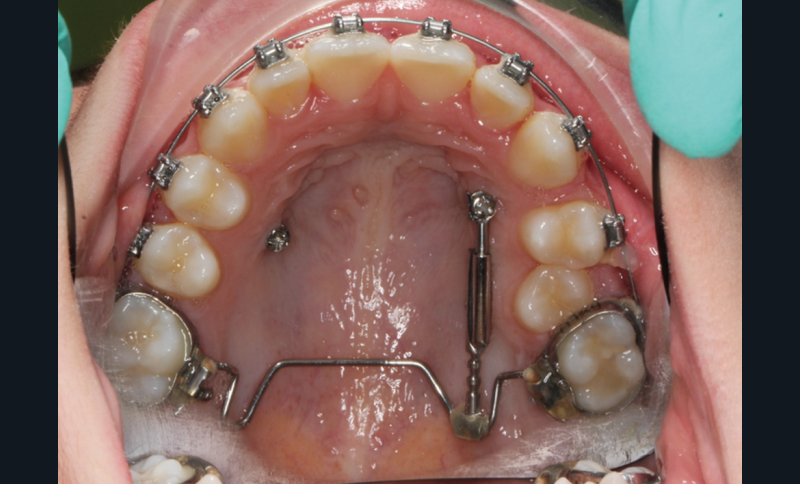

À côté de la coopération moindre qu’ils exigent, les ancrages squelettiques présentent également l’avantage de répondre à des indications très variées : correction des sourires gingivaux (Dr Skander Ellouze, fig. 3a-c), distalisation ou mésialisation molaire, supports pour les masques faciaux, mini transpalatin sur vis après expansion, ressorts de rétraction pour mettre en place les canines incluses sans léser les racines des dents adjacentes [3] (Dr Stéphane Renger, fig. 4) ou appareils d’expansion maxillaire (Dr Hans Winsauer, Dr Guido Sampersmans, fig. 5a-c)…